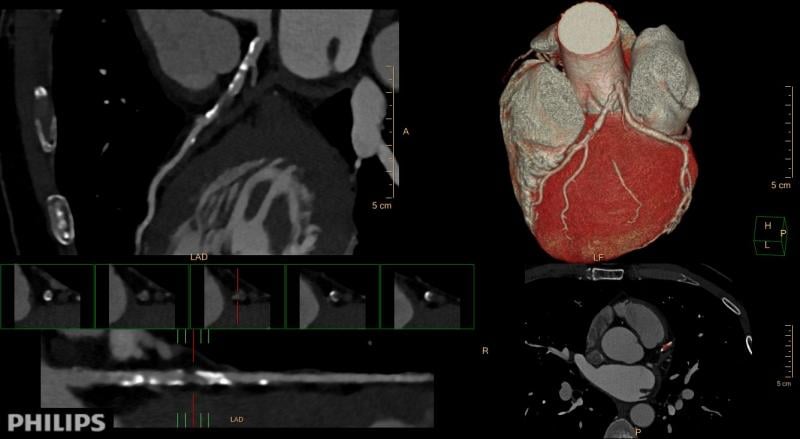

This channel contains news about the Society of Cardiovascular Computed Tomography (SCCT), including coverage of its annual meeting and links to recently released practice guidelines. SCCT is a leading resource for the subspecialty of cardiac computed tomography angiography (CTA or CCTA).

The Society of Cardiovascular Computed Tomography (SCCT) annual meeting offers an in-depth review of all aspects of ...

Here is a recap of some of the top trends and new technology at the Society of Cardiovascular Computed Tomography (SCCT) ...